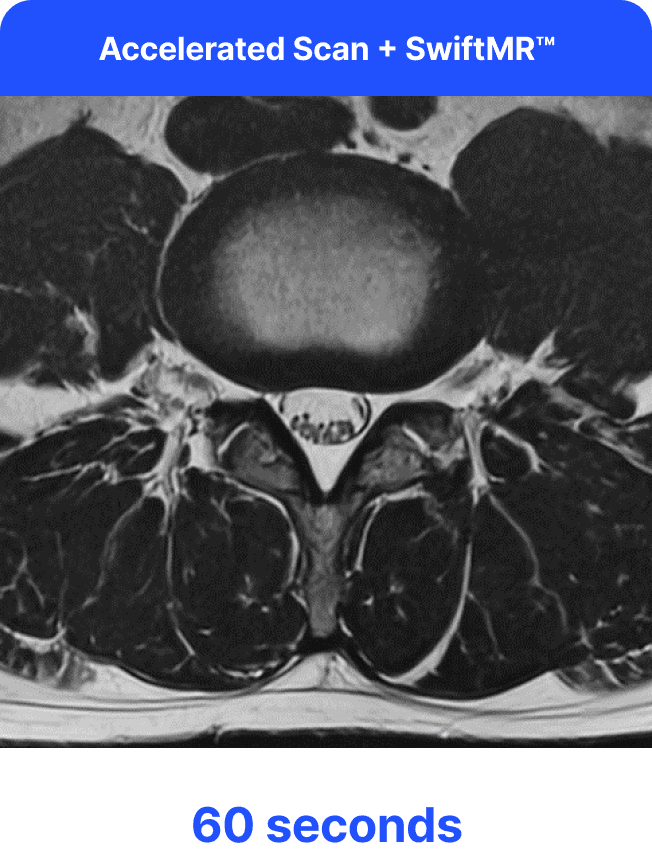

SwiftMR is a deep learning solution that enables MRI scan time reduction, enhancing patient comfort without sacrificing image quality. The solution enables radiology centers to achieve new levels of productivity and efficiency, as shorter scan times increases patient throughput — unlocking opportunities for revenue and growth.

Our team will optimize MRI protocols to accelerate scans, initially producing faster yet low-quality images. SwiftMR's deep learning model is then employed to enhance the accelerated scans, effectively transforming them into high-quality images.